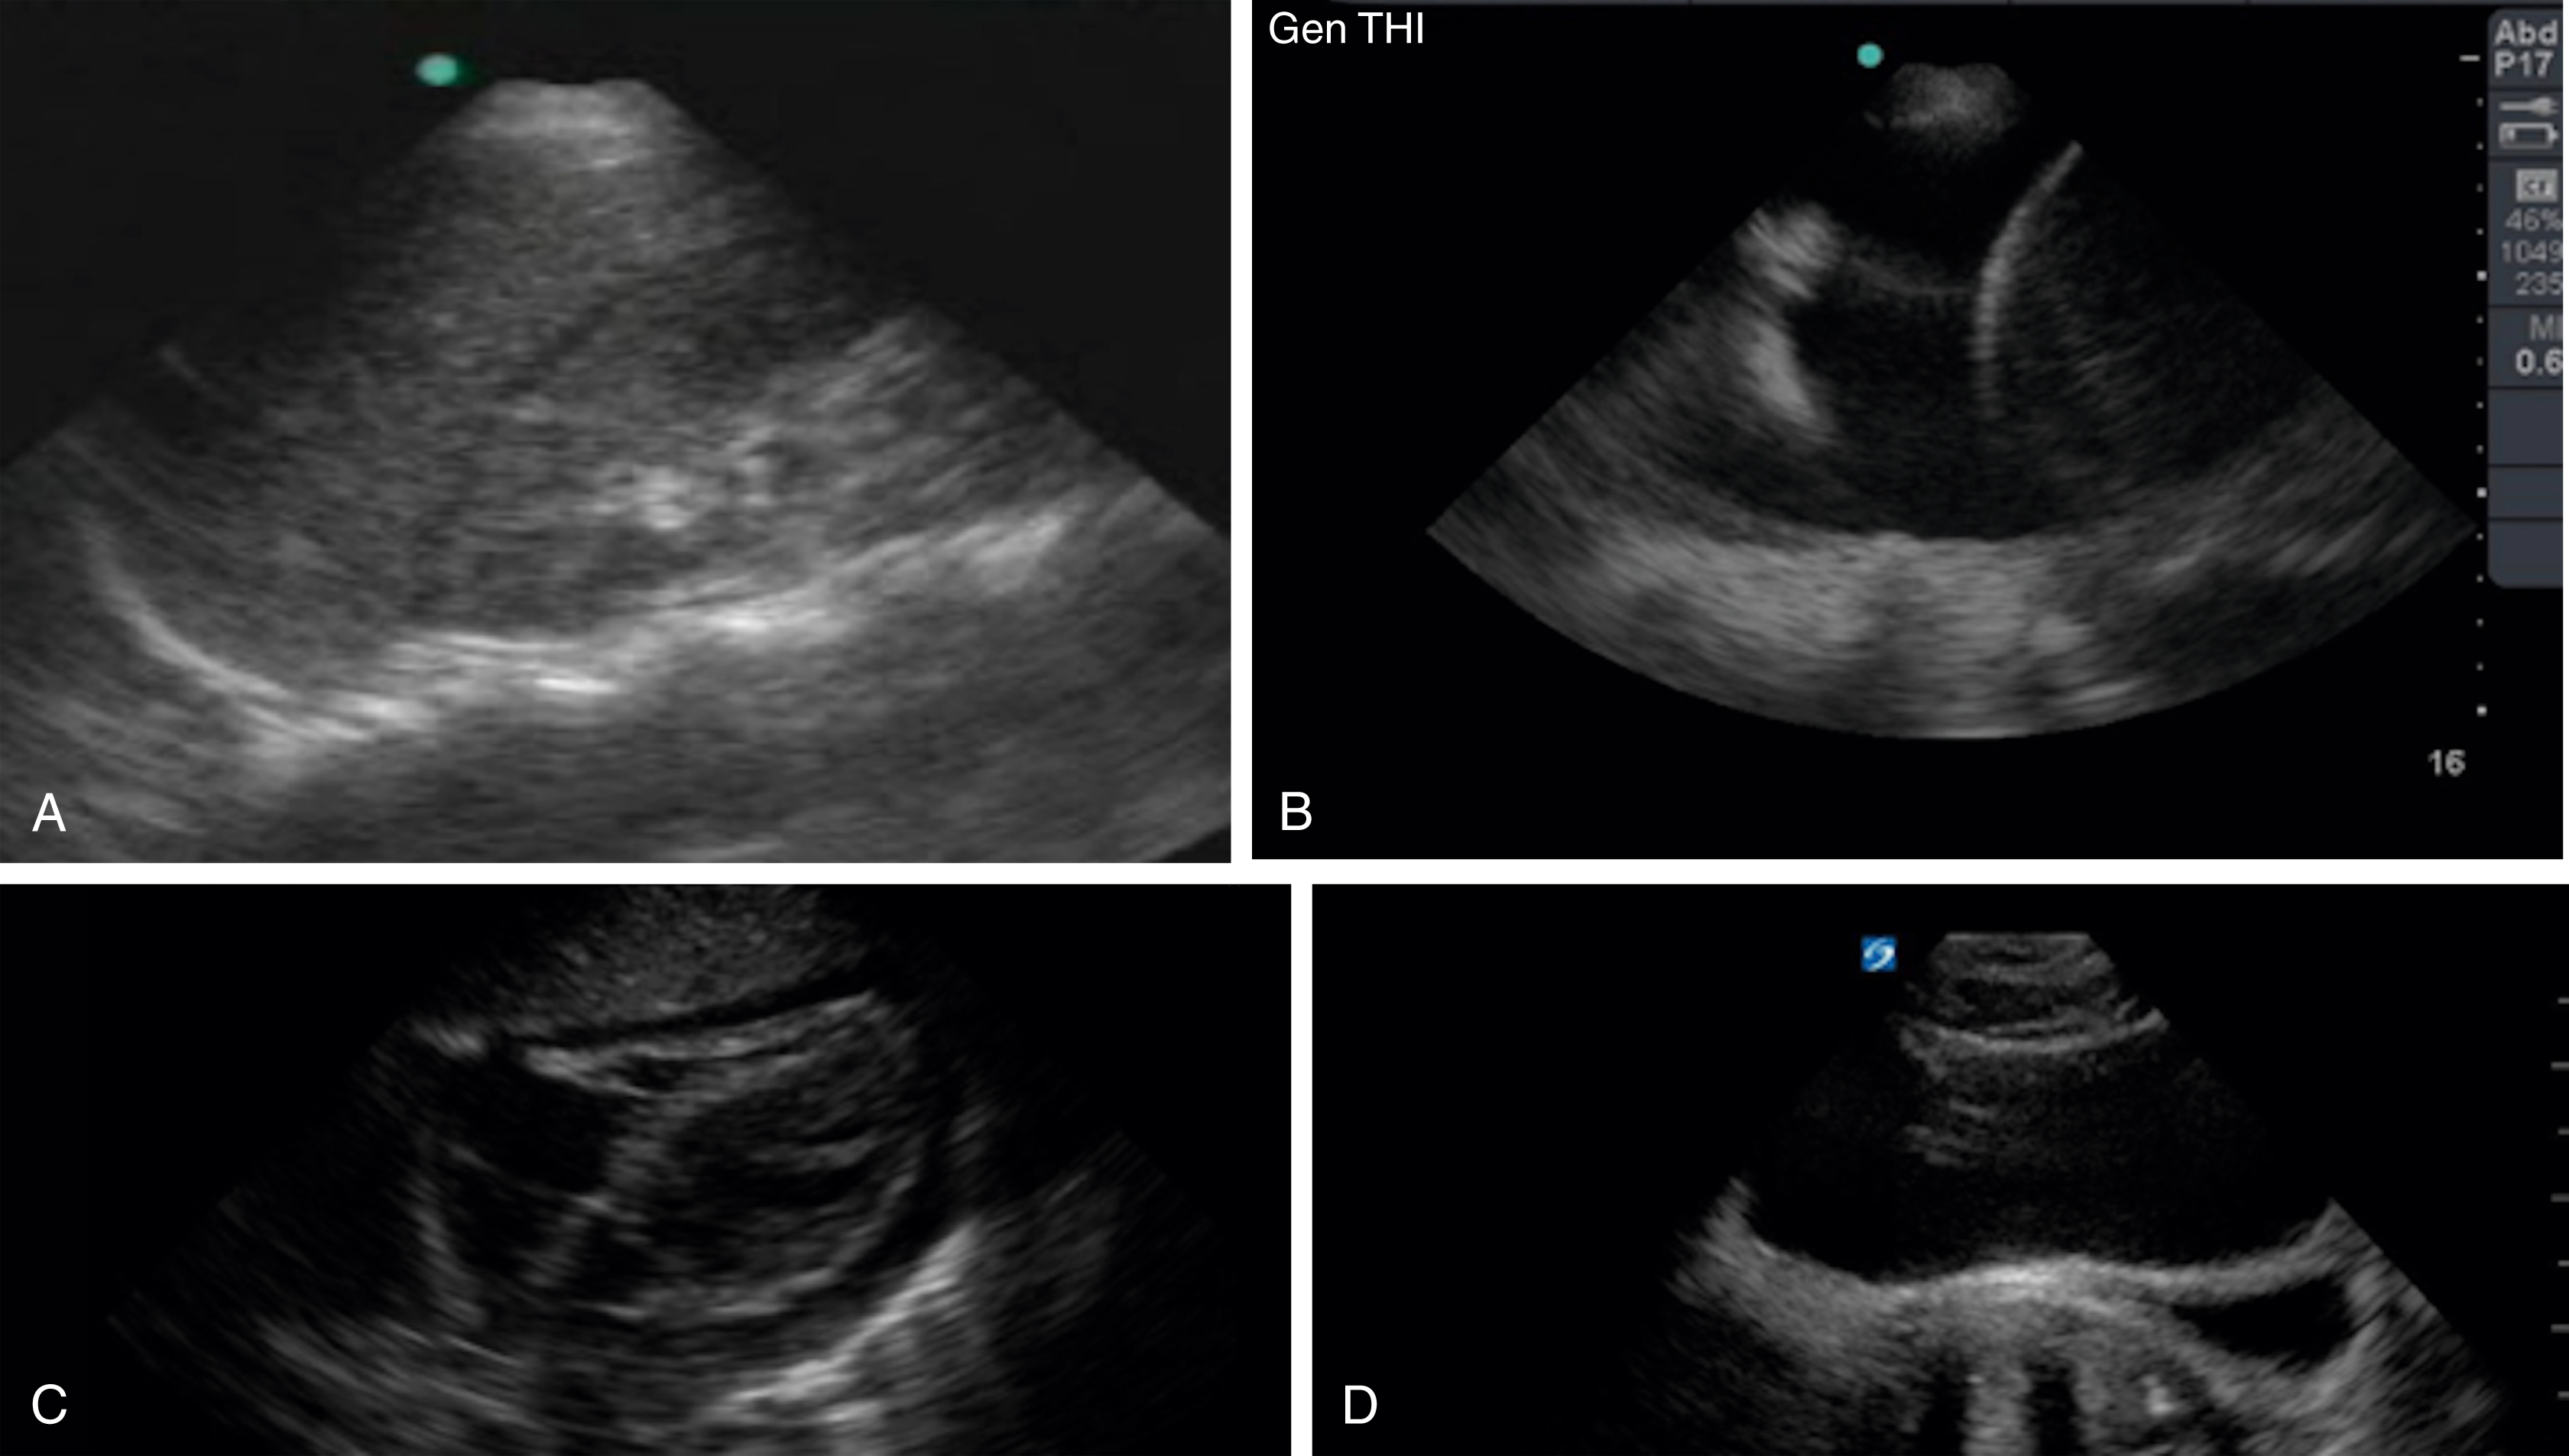

RV assessment is another useful tool for the emergency clinician when pulmonary embolism (PE) is high on the differential. With increasing right heart pressure, the RV dilates, squeezes poorly, and ultimately develops flattening of the interventricular septum, creating the “D” sign ( Figs. e3.12, e3.13 , and Video e3.11 ). The sparing of the RV apex is called the McConnell sign and is highly suggestive of PE. ,

Apical 4-chamber view of the heart with an enlarged RV.

Parasternal short axis view with “D” sign signifying increased RV pressure.